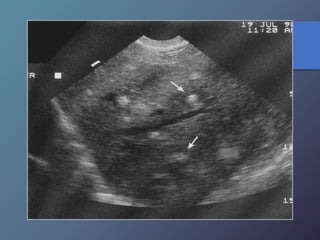

Metástasis

• Su incidencia depende del tipo de tumor.

• Localizaciones mas frecuentes del TU primario:

vesícula biliar, colon, estomago, páncreas, mama y

pulmón.

• Pueden presentar una sola lesión hepática, aunque

suelen tener múltiples masas focales.

Mt Hiperecoicas

• Ecográficamente se presentan las lesiones

de tamaño variable con presencia de un

halo hipoecoico.

• Diferenciar lesiones malignas de benignas

por presencia de halo hipoecoico.

• Se describen como lesiones ecógenas,

hipoecoicas, en diana, calcificadas,

quísticas y difusas.